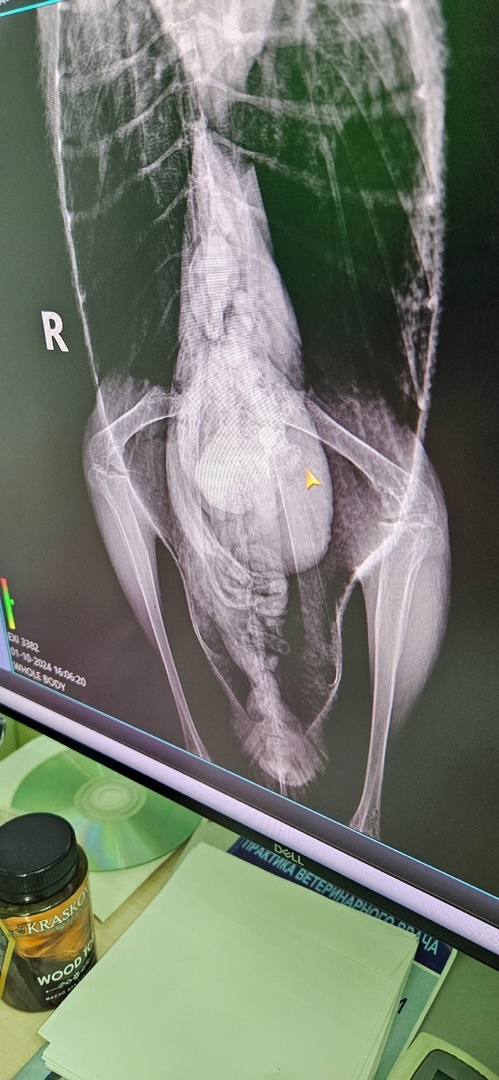

Свозили нашего лебедушку сегодня на рентген. Лебедь сильно болеет, у него помимо внешней деформации крыльев, воспалены лапки, но это не так страшно, страшнее всего видеть было рентгеновские снимки.

В птицу стреляли. Дроби по всей длине шеи, их смогут вытащить местные специалисты. Но на снимке в желудке бедного животного было обнаружено рыбацкое грузило с леской. Скорее всего, эти рыбацкие снасти, которые находятся внутри, приведут к серьёзным последствиям, и их нужно срочно доставать. Нам предстоит ещё сдать анализы и постараться вылечить это ни в чем не повинное создание.

Мы объявляем срочный сбор средств. На данный момент нам необходимо оплатить 7 рентгеновских снимка - 4200 р. Нужно сдать анализы - от 2000 р. и купить необходимые лекарства в достаточно большом количестве (на сумму более 20 тысяч), т.к. наш Саша достаточно крупная птица, весит 5,500 кг и нуждается в больших дозировках лекарственных средств. Эндоскопическая операция по удалению рыбацких снастей будет стоить от 10 000 рублей.